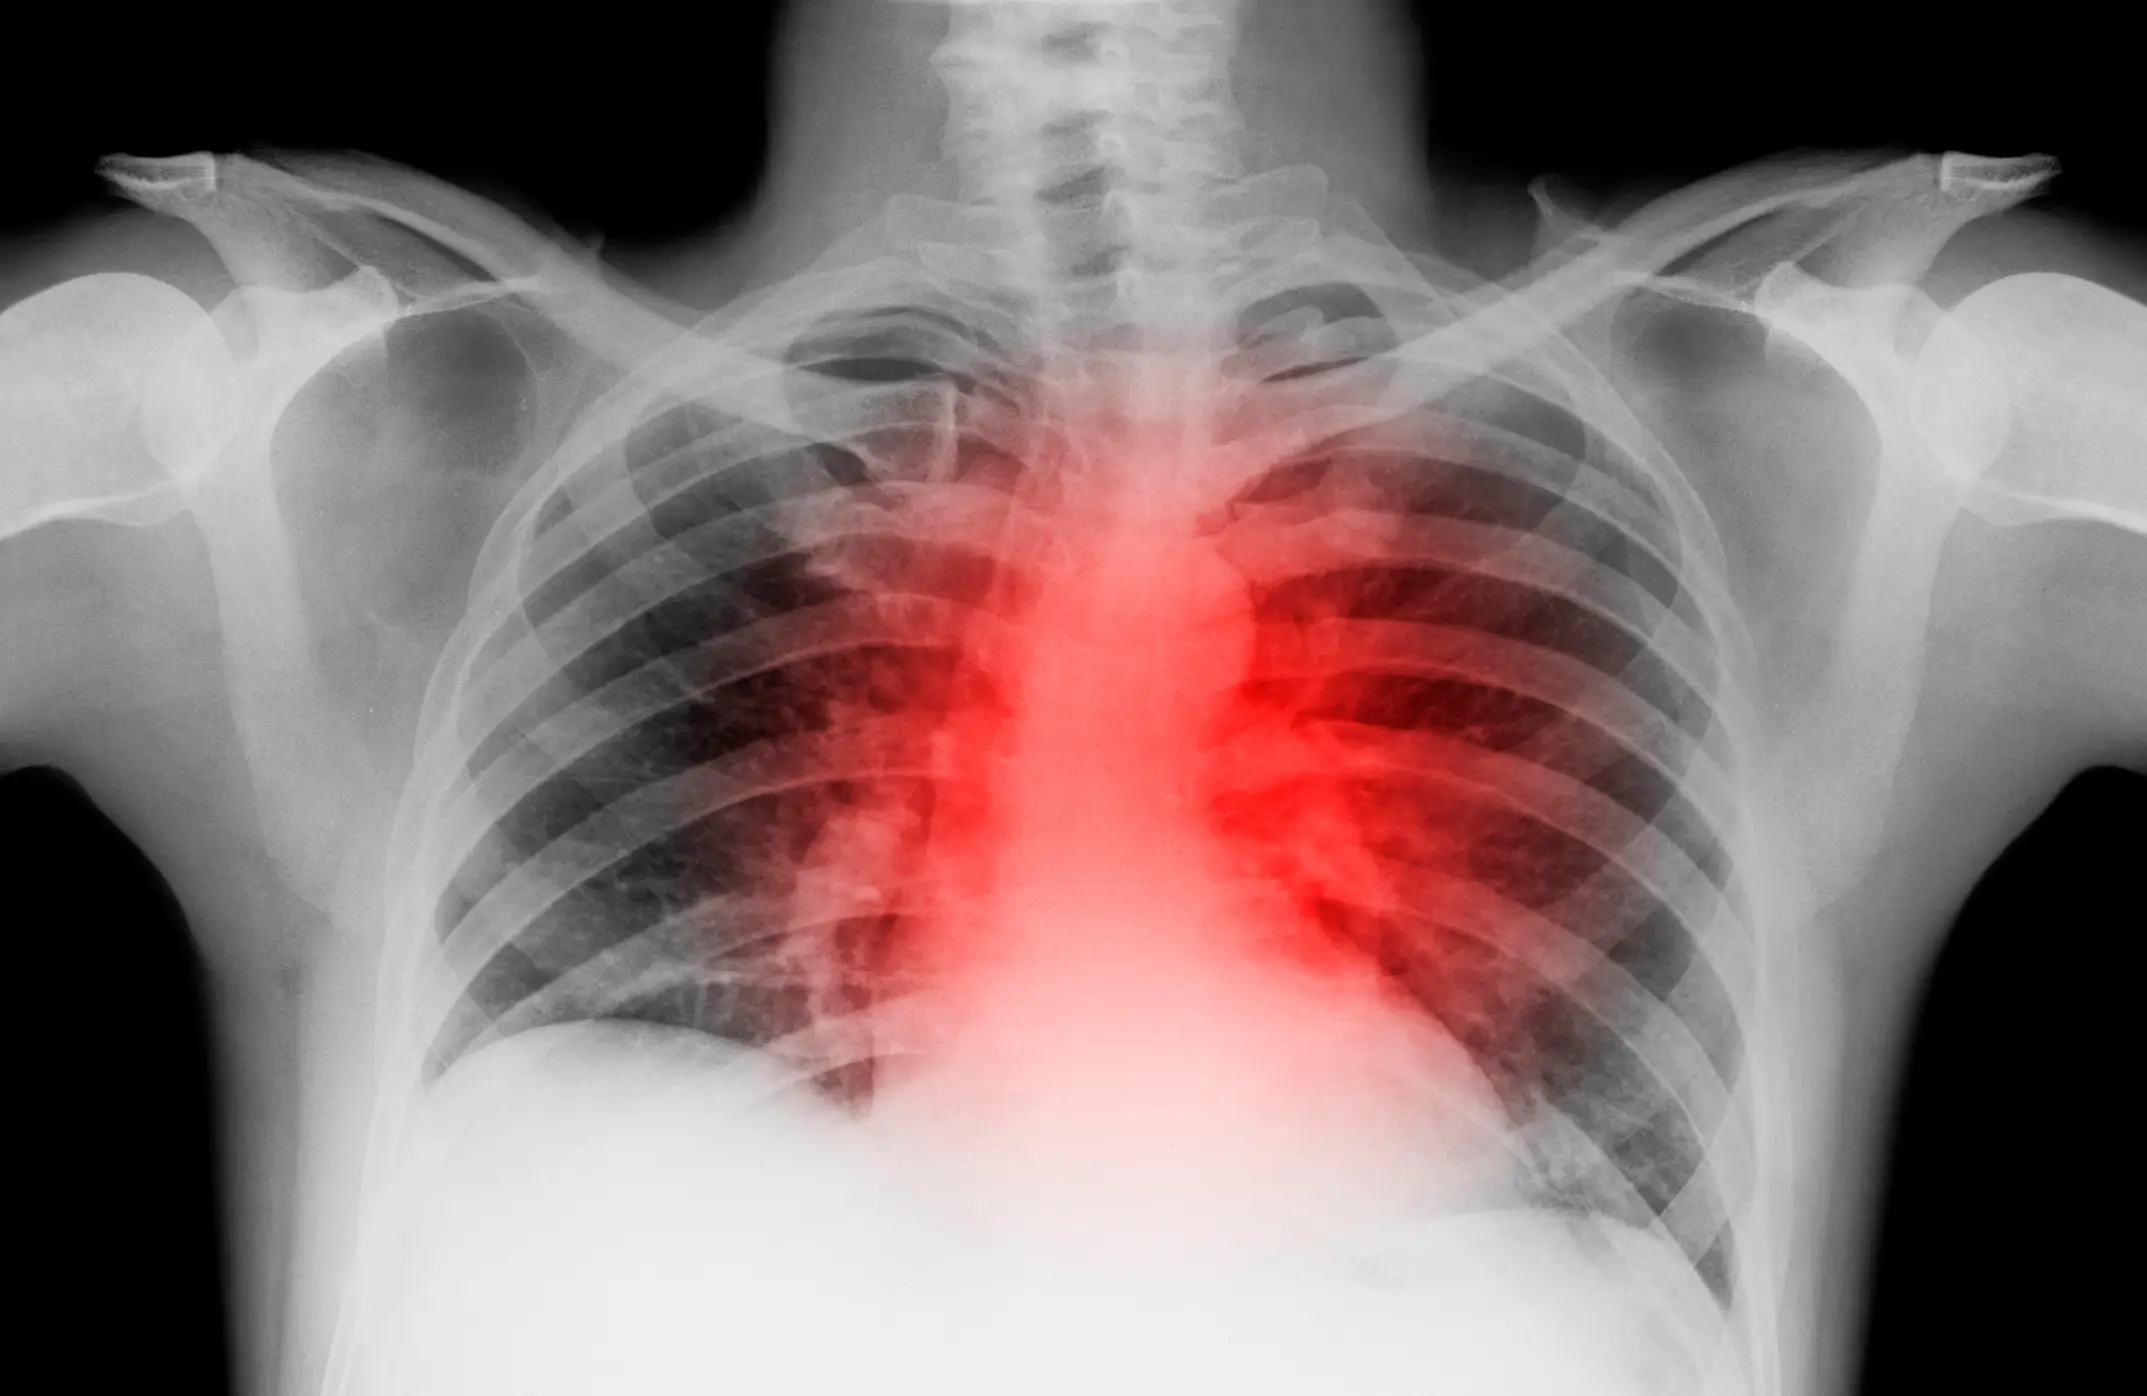

EXPERT SAYS THERE'S ONE MAIN SIGN OF HEART DISEASE EVERYONE SHOULD KNOW

DOCTOR'S WARNING OVER CERTAIN SLEEPING POSITION THAT COULD BE SIGN OF DEADLY HEART FAILURE

According to the NHS, things which can have a negative impact on your heart health include diet, poor blood pressure, smoking and exercise.

It's also important to note the test is also an educated guess and if you have any medical concerns, you should check-in with your GP.